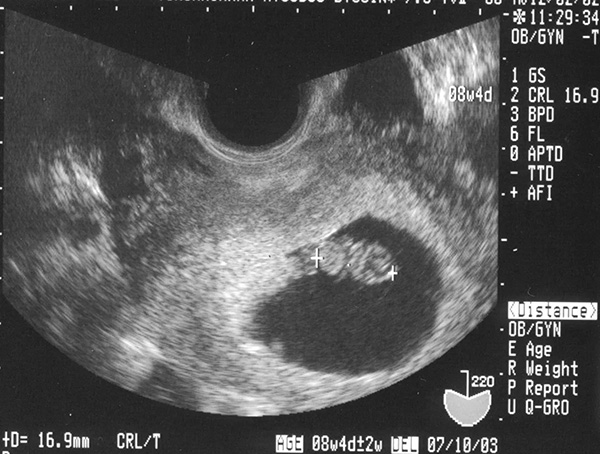

Ảnh siêu âm thai 6 tuần

– GSD (Kích thước túi ối): Chỉ số GSD được xác định vào những tuần đầu của thai kỳ, lúc thai nhi chưa hình thành hết các cơ quan, bộ phận cơ thể. Lúc này, chỉ số GSD là 14-25mm

– CRL (Chiều dài đầu mông): Vào thời điểm thai 6 tuần thì chỉ số này bình thường là 4-7mm